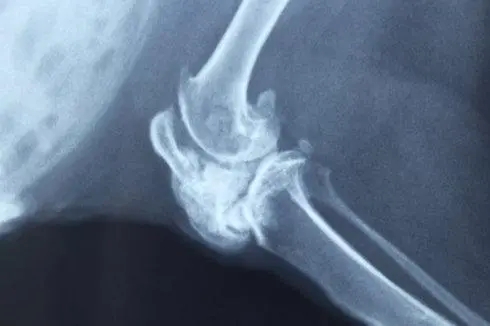

1.1.X線所見為骨內(nèi)的溶骨性病變,可有鈣鹽沉積,大部分腫瘤生長(zhǎng)緩慢,少數(shù)生長(zhǎng)迅速。在骺干骺端,腫瘤為偏心性;在骨干,則位于骨干的中心。

1.2.中心性軟骨肉瘤可表現(xiàn)為邊界模糊的溶骨,有或無皮質(zhì)骨中斷,由于軟骨傾向于鈣化和骨化,腫瘤內(nèi)可出現(xiàn)不透X線區(qū),鈣化經(jīng)常發(fā)生在軟骨小葉的周圍,無一定結(jié)構(gòu),其特征為不規(guī)則的霧狀顆粒、結(jié)節(jié)或不透X線的環(huán)。

1.3.由于瘤壁骨嵴,腫瘤可產(chǎn)生泡狀或面包屑樣外觀。如鈣化致密,腫瘤可呈不透X線的金屬樣。如腫瘤浸潤(rùn)到松質(zhì)骨的髓腔而未破壞骨小梁時(shí),鈣沉積和反應(yīng)性骨增生可呈不透X線均勻一致的海綿骨樣。如腫瘤浸潤(rùn)松質(zhì)骨未破壞骨小梁且無鈣化時(shí),骨內(nèi)的腫瘤部分可不顯影,在這種情況下,如果不借助骨掃描、CT和MRI,中心性軟骨肉瘤的診斷困難且晚。

分化良好的中心性軟骨肉瘤鈣化多,而Ⅲ級(jí)中心性軟骨肉瘤及反分化中心性軟骨肉瘤鈣化少且粘液區(qū)多。

皮質(zhì)骨可以很薄,內(nèi)部呈扇貝狀,在一些區(qū)域可有中斷。有時(shí)由于腫瘤膨脹緩慢,皮質(zhì)骨發(fā)生增生,可顯得增厚。這種增厚的皮質(zhì)骨表現(xiàn)相當(dāng)?shù)湫?,表明其已被腫瘤所浸潤(rùn)。